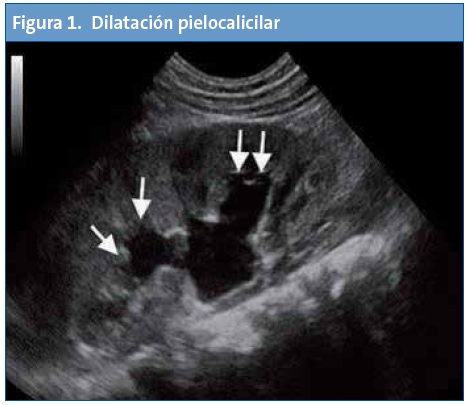

La ecografía puede ser de utilidad tanto para screening de patologías como para diagnóstico y/o seguimiento. Es una herramienta de apoyo a nuestra orientación diagnóstica basada en una clínica y una exploración física.

En Atención Primaria el mayor rendimiento se obtiene de la exploración abdominal seguida del estudio de la zona cervical, partes blandas, aparato genital, pulmón y aparato locomotor.